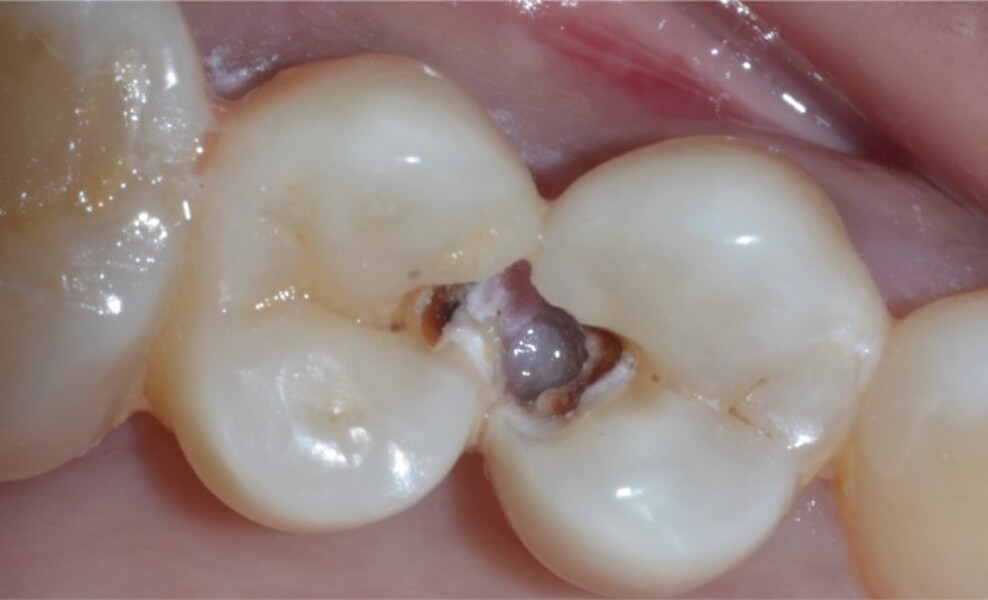

Predictable posterior restorations